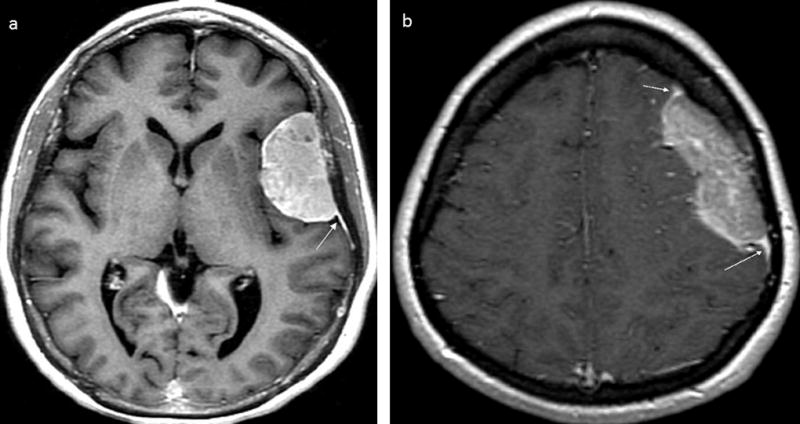

FIGURE 1. Axial post-gadolinium T1-weighted imaging of dural masses.

(a) Brain MRI image showing a meningioma with avid enhancement including dural tail and characteristic hyperostosis of the overlying calvarium. (b) Brain MRI image showing a DL with lesser enhancement than the dural tail; it also shows an irregular medial border of DL which is atypical of meningioma. White arrows denote dural tails.

The median age at tumor diagnosis of our 26 patients was 50 years (range, 30–77 years) and 20 (74%) were women (Table 1). The most frequent symptoms were seizures (41%), headache (33%) and cranial nerves palsies (30%). Median time from initial symptoms to tumor diagnosis was 8 weeks (range, 1 to 90 weeks). All lesions were exclusively extra-axial, and tumors presented in the frontal lobe in 6 (23%) patients, temporal lobe in 4 (15%), occipital lobe in 3 (12%), the cavernous sinus in 3 (12%), the cerebellopontine angle in 2 (8%), the falx cerebri in one (4%) and was suprasellar in one (4%) patient. Six patients presented with multifocal disease. Pre-operative MRI was available for our review in 17 patients. Sixteen (95%) had lesions with an enhancing dural tail. In 10 (63%) of these 16 patients, lymphoma enhancement intensity was less than that of the enhancing dural tails (Figure 1). Underlying vasogenic edema was seen in 56% of patients, hyperostosis/erosion of the contiguous bone in 3 (18%), calcification in one (6%) and central vascular pedicle in one (6%). In 6 patients, diffusion was available for quantification using apparent diffusion coefficient (ADC) maps. The median ADC was 0.598 × 10−3mm2/s (range, 0.322–0.833).

To our knowledge, these 26 patients represent the largest published series on DL. DL is more common in middle-aged women, and the most frequent symptoms at presentation are seizure and headache (1, 2). Almost 70% of our patients underwent resection as the lesion was thought to be a meningioma. We reviewed pre-operative MRIs in an effort to identify radiographic features for this patient population. Dural tails were observed in 95% of patients. In ~60% of the patients, we observed that lymphoma enhancement was less intense than enhancement of the reactive dural tail. This differs from meningioma, where the intensity is equal. The ADC measurements in the subset of patients with evaluable tumors confirmed restricted diffusion comparable to what has been reported in PCNSL (0.55–0.58 x10-3mm2/s), and lower than those reported in meningioma (0.85–0.96 x10-3mm2/s) (12–14). Diffusion may be variable in atypical or malignant meningiomas with lower ADC values, but diffusion measurements may be helpful in differentiating DL from meningioma (15). In addition, underlying vasogenic edema was seen in 56% of patients, which is an uncommon finding in typical grade I meningiomas.